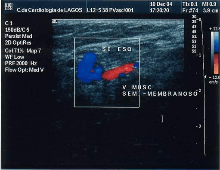

The small saphenous vein (SSV), runs along the posterior aspect of the leg as far as the popliteal region, in the upper calf. Here it enters the popliteal space which is located between the two heads of the gastrocnemius muscle where it usually drains above the knee joint in the popliteal vein or a little less often in the great saphenous vein (GSV) or other deep muscular veins of the thigh.[52] The use of ultrasonography has allowed a number of variations to be shown at this level; when no contact is made with the popliteal vein it might be seen to drain in the GSV, at a variable level; or, it may merge with the Giacomini vein and drain in the GSV at the superior 1/3 of the thigh. It can also but rarely, drain in the vein of the semimembranosus (thigh muscle) (shown below). Usually though, it connects with a perforator vein at its middle 1/3.[22] To check for insufficiency, the Paraná maneuver is very useful.[35]

![]() Insufficiency from the SSV at sapheno-popliteal junction |

![]() Insufficiency from the SSV flooded by the vein of the semimembranosus muscle |

![]() SSV variant draining in the vein of the semimembranosus muscle |